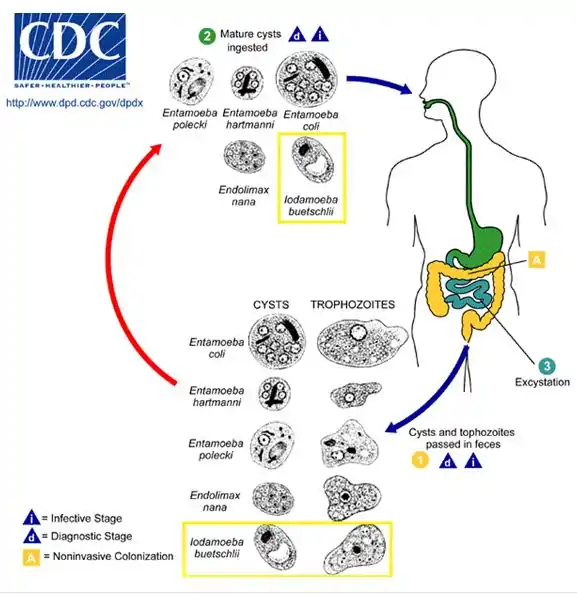

Lifecycle

trophozoite in cecum & colon-->cyst in feces- ingested-->trophozoite in cecum & colon[4]

Named for Otto Bütschli by Prowazek in 1912, Iodamoeba buetschlii is a nonpathogenic parasitic ameba, commonly found in the large intestines of people, pigs and other mammals.

The distribution of I. buetschlii is worldwide. Most likely to be the original host, pigs are often targeted with I. buetschlii. I. buetschlii is identified as a non-pathogenic parasite. Often, this parasite is mistaken as a pathogenic parasite because non-pathogenic and pathogenic parasites have the same characteristics. In terms of illnesses, humans have a low prevalence of I. buetschlii (4-8%). I. buetschlii is an indicator of oral-fecal contamination and humans may experience diarrhea.[3][4]